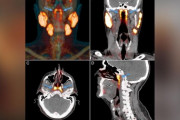

【衝撃】オランダ人、人体に隠された新臓器を発見